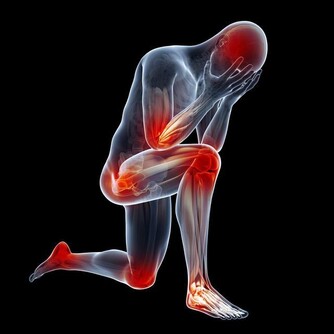

2、手腳冰冷

有些人一到秋冬季節,人體沒有感覺到寒冷,但是手腳會一直處於冰冷不溫的狀態,這就是脾虛生寒的表現。